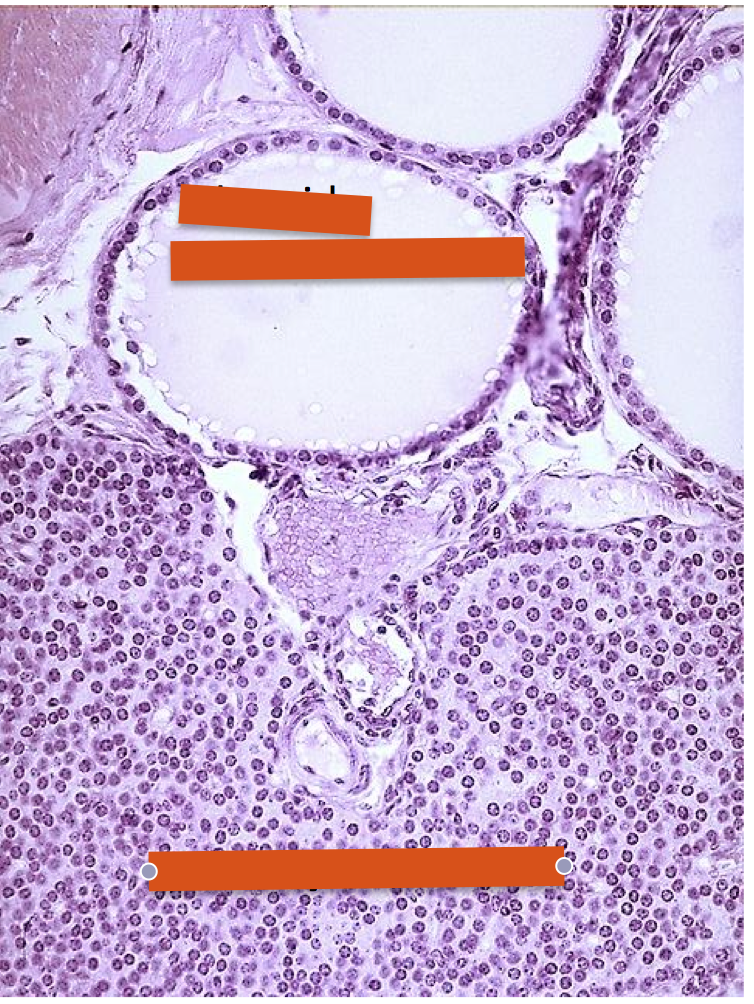

thyroid gland

***follicular cells also known as principal cells